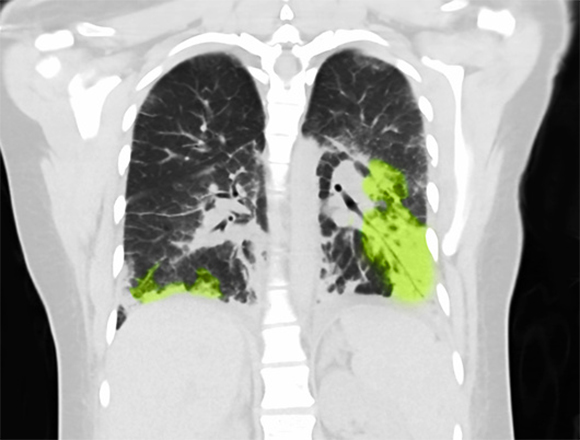

בשנת 2019 נרשמה עלייה חדה במספר האשפוזים בארצות הברית עקב שימוש בסיגריות אלקטרוניות. צילום ריאות של אישה בת 19 עם נזק מעישון סיגריות אלקטרוניות | מקור: Steven Needell / Science Photo Library

עקב הזמן המועט יחסית שחלף מאז פיתוח הסיגריה האלקטרונית, שלא מאפשר לזהות נזקים ארוכי טווח עקב השימוש בה, המחקר על השלכותיה הבריאותיות לא מספק תשובות ברורות. לדוגמה, רק בשנת 2019 זיהה המרכז לבקרת מחלות ומניעתן בארצות הברית (CDC) תסמונת חדשה שנקראת "נזק לריאות המקושר לשימוש בסיגריות אלקטרוניות או במוצרי אידוי", או איוואלי (EVALI) בקיצור, בעקבות עלייה חדה שנרשמה במספר האשפוזים עקב שימוש בסיגריה אלקטרונית. התסמינים כללו קוצר נשימה, כאבים בחזה, חום גבוה, דופק מהיר, שיעולים, כאבי בטן והקאות. בתוך שנה אחת נרשמו 2,800 אשפוזים עקב איוואלי, ו-68 מהם הסתיימו במוות. רוב מקרי איוואלי אלה נגרמו ככל הנראה משימוש בוויטמין E אצטט בנוזל האידוי.

כיום כמות מקרי האיוואלי פחתה, אך התופעה לא נעלמה. נראה כי הסיגריות האלקטרוניות עלולות לפגוע ברקמת הריאה באמצעות כמה וכמה מנגנונים, שפועלים בטווח הרחוק והקרוב. אחד מהם הוא עידוד של שינויים גנטיים (מוטציות) בתאי הריאה וכתוצאה מכך פגיעה בתפקוד מערכת הנשימה. אחרים הם עירור תגובה דלקתית בריאות, או קריסת ריאה (פנאומוטורקס, או חזה אוויר).

נוסף על איוואלי ופגיעות קצרות טווח אחרות, חוקרים מנסים להעריך את ההשלכות הבריאותיות הצפויות מהסיגריות האלקטרוניות בטווח הרחוק יותר. הנזק העיקרי צפוי לאיברים הראשונים שפוגשים את החומרים הנשאפים: הפה, האף, קנה הנשימה והריאות.

התוכן המזיק שנשאף מגיע לא רק מהנוזל המאודה, אלא גם מהחלקיקים המתכתיים המרכיבים את הסיגריה עצמה, כגון ניקל, אלומיניום ועוד. בשימוש ממושך כל אלה מעלים את הסיכון לסרטן הריאות, האף והסינוסים. תופעות נוספות שנקשרו עם שימוש מתמשך בסיגריות אלקטרוניות הן קוצר נשימה ושיעולים, כאבים בחזה, כאבי ראש, חרדה ועוד.